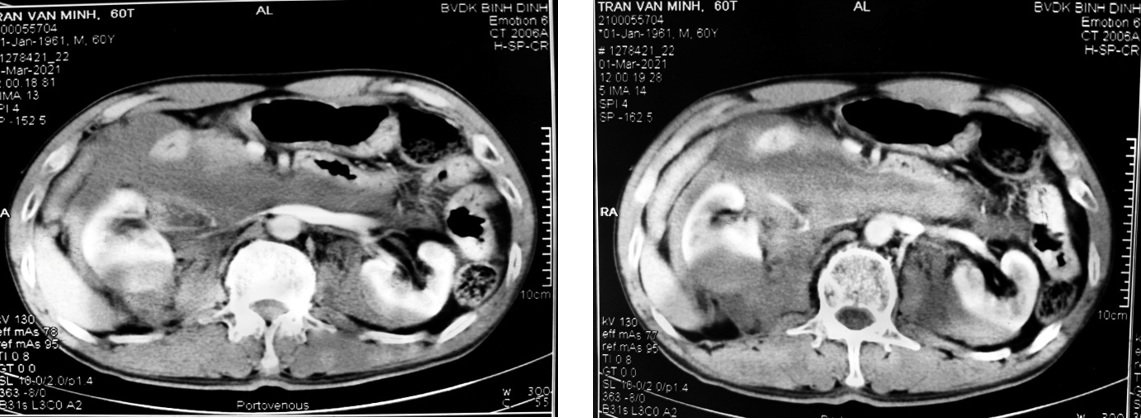

Bệnh nhân vào viện trong tình trạng tỉnh táo,da niêm mạc mắt hồng, mệt nhiều mạch 100 lần/phút, huyết áp 80/40 mmHg, nhịp thở 20 lần/phút, bụng chướng, ấn đau nhiều thắt lưng (P), nước tiểu qua sonde đỏ tươi. Chụp CT-Scanner bụng có cản quang vỡ cực dưới 2 thận độ IV, tụ máu khoang quanh thận và cạnh thận 2 bên. Tụ máu khoang sau phúc mạc d#74x105 mm, có dấu hiệu xuất huyết hoạt động bên trong; thận móng ngựa. Xét nghiệm công thức máu HC: 4,45 x 1012/L, Hb: 138 g/L, Hct: 41,4%. Đến 12 giờ 30 phút HA: 70/40 mmHg được sử dụng thuốc vận mạch; xét nghiệm công thức máu lần 2 HC: 2,93 x 1012/L, Hb: 91,9 g/L, Hct: 28,8%; truyền 750ml hồng cầu khối. Đến 19 giờ huyết áp vẫn phụ thuộc vào thuốc vận mạch. Quyết định mổ cấp cứu.

Hình ảnh CT-Scanner thận móng ngựa bị vỡ 2 cực dưới